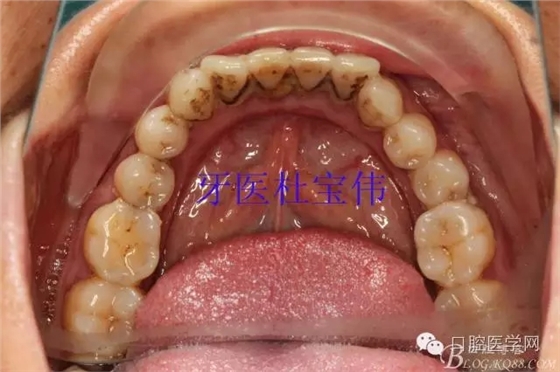

病例二術(shù)前照片